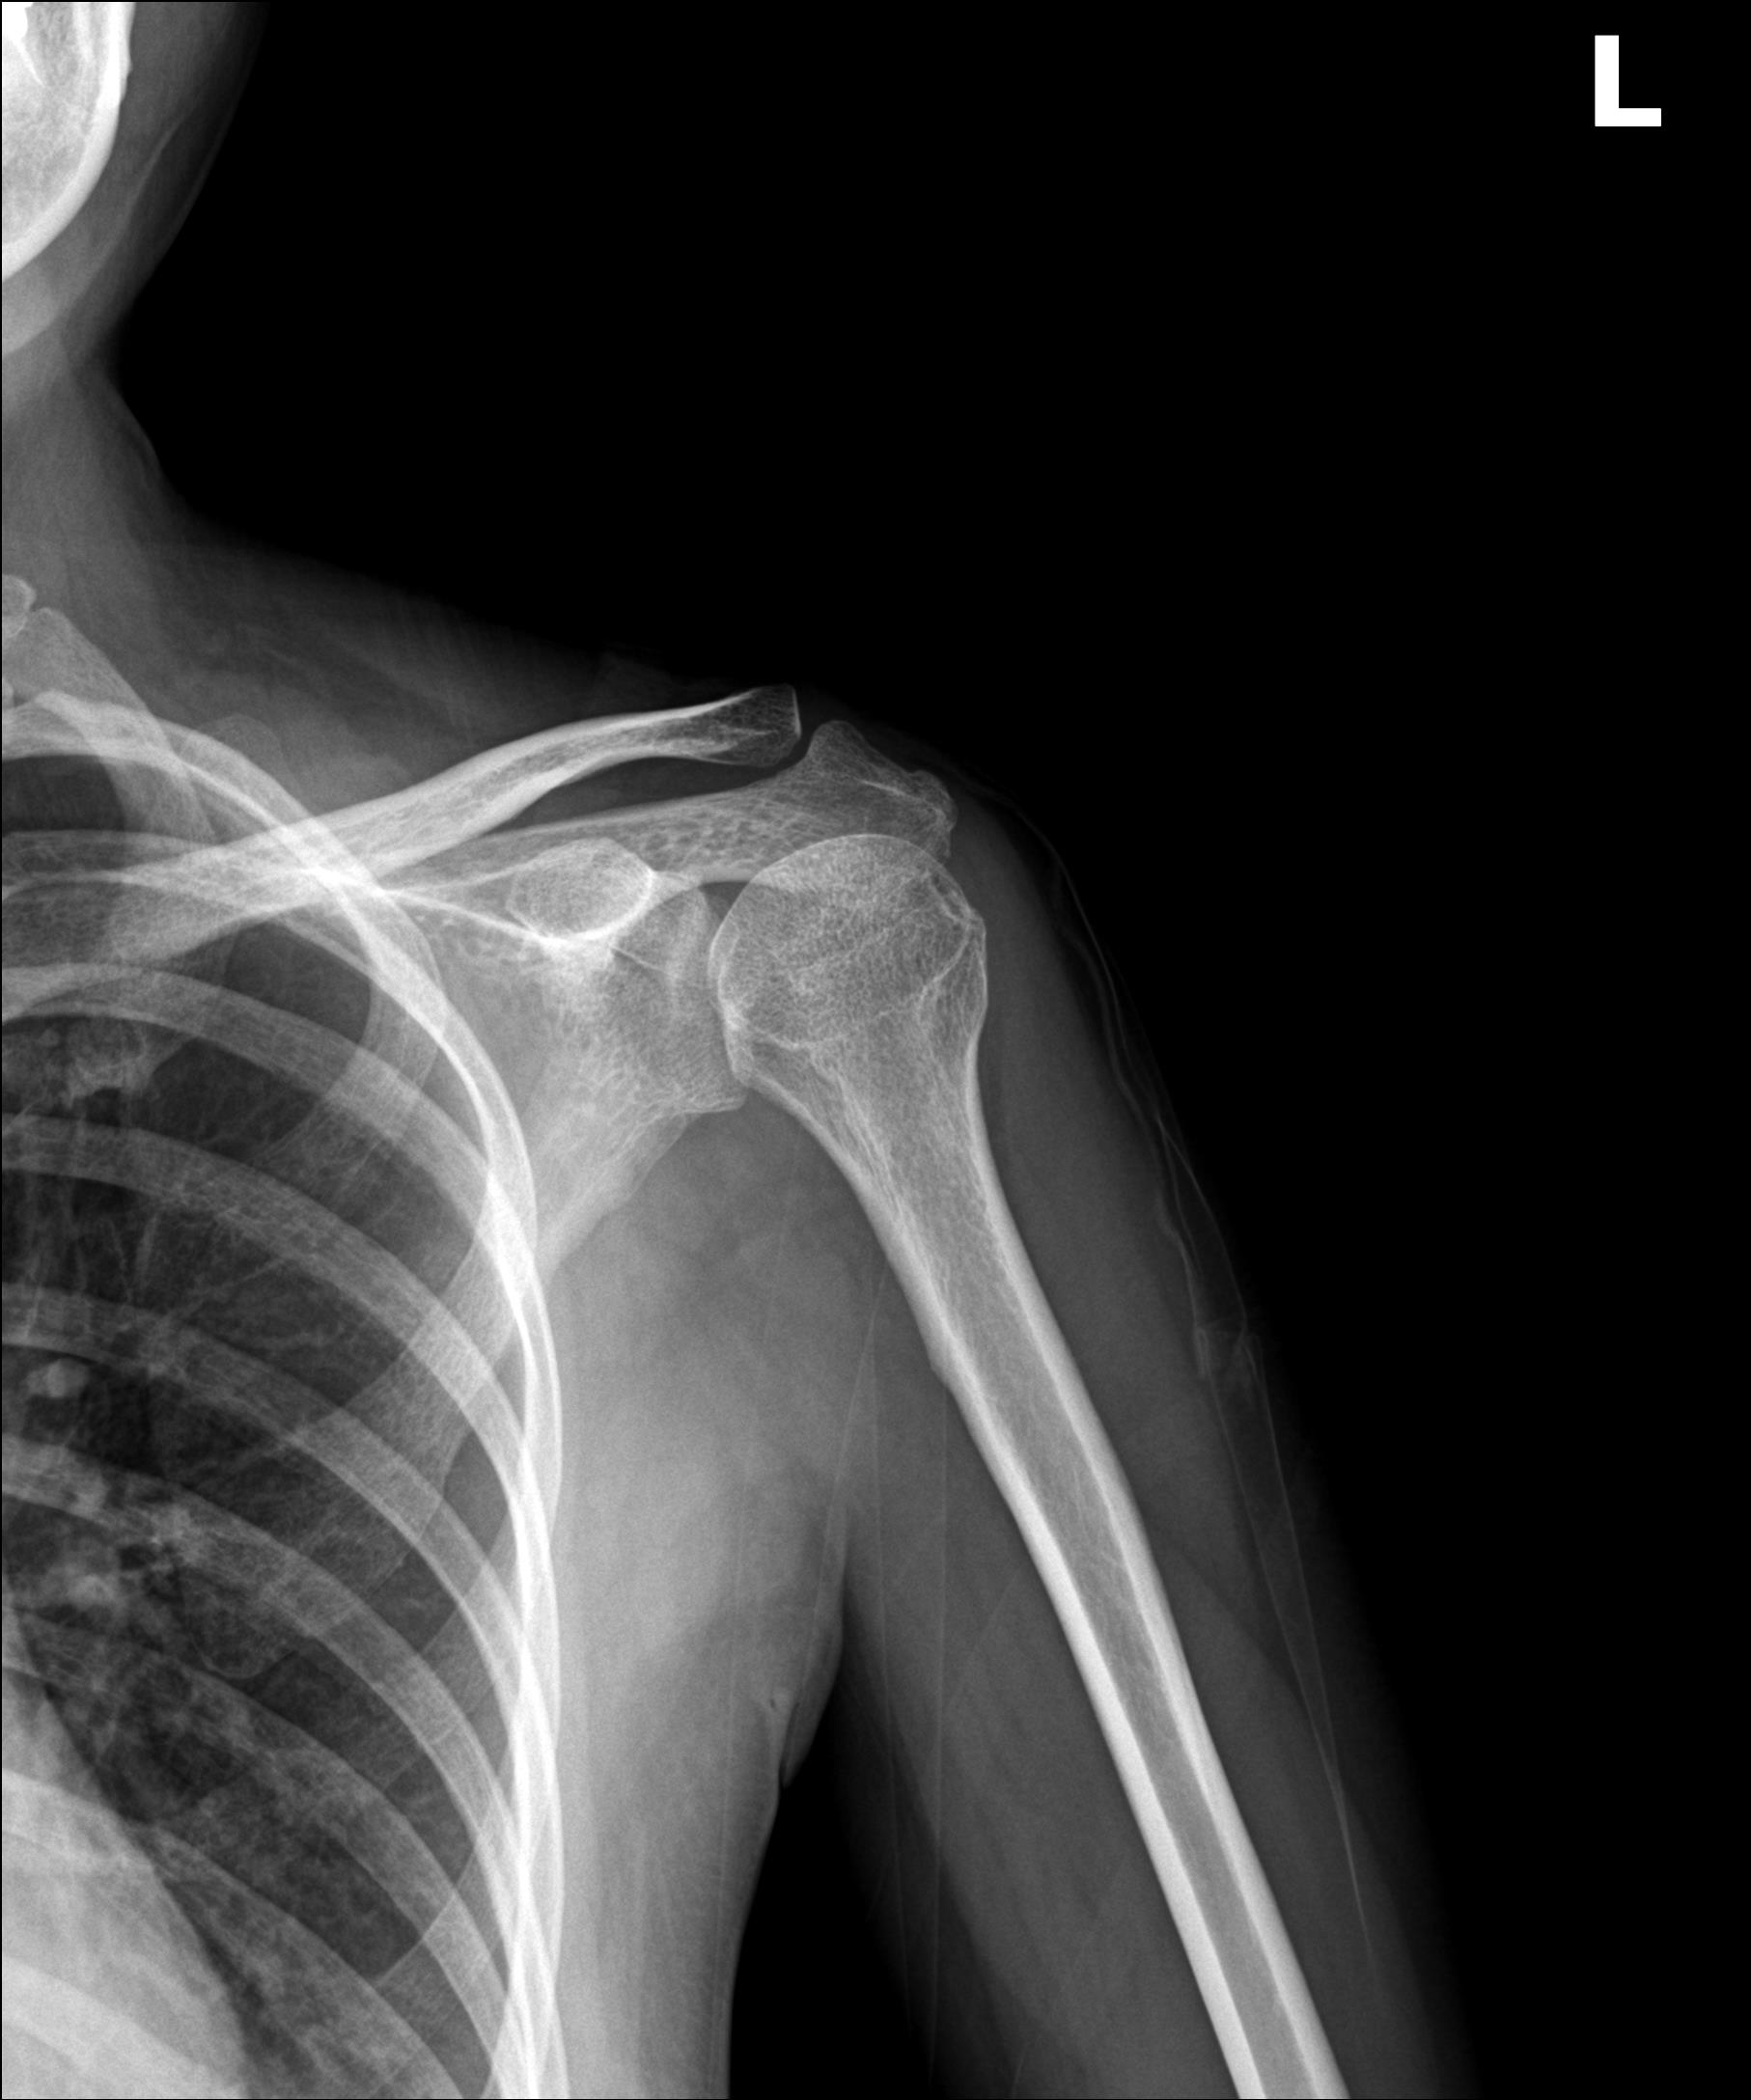

케이스 2: 휴지기 중형 석회 (1회 제거)

환자: 40대 여성, 좌측 어깨 야간통 1년

시술 전:

약 1.2cm 석회, 휴지기

충격파 10회 + 주사흡입술 2회 받았으나 호전 없음

시술 후:

1회 분쇄흡입술로 제거

야간통 소실, 수면 가능해짐